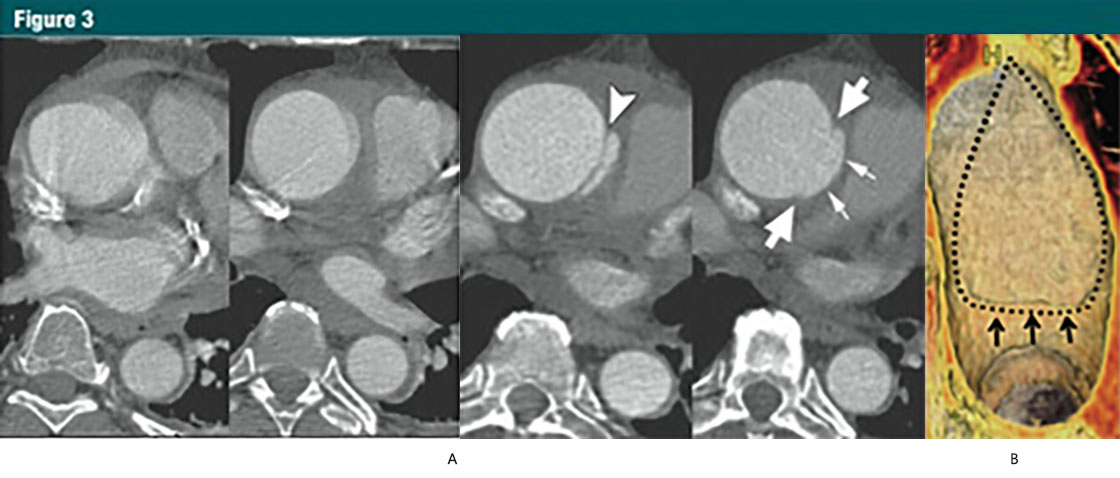

圖3 升主動(dòng)脈局限性內(nèi)膜撕裂

(A)上方:無心電門控的CTA顯示升主動(dòng)脈運(yùn)動(dòng)偽影,模糊;下方:12小時(shí)后,心電門控 CTA示:升主動(dòng)脈近端內(nèi)膜皮瓣(箭頭),伴隨一個(gè)侵蝕邊緣的局限性內(nèi)膜撕裂。局限性內(nèi)膜撕裂的邊緣(大箭頭)和主動(dòng)脈壁破壞形成的突起(小箭頭)清晰可見。這些微妙細(xì)節(jié)如果沒有使用心電門控是不可見的。

(B)VR重建顯示腔內(nèi)一側(cè)6cm長的損傷。一個(gè)小的破損皮瓣(細(xì)箭)代表撕裂的起始端,并一直延伸到主動(dòng)脈弓的近端。虛線,代表撕裂的邊緣。(轉(zhuǎn)載,許可,引用24。)

少數(shù)有中層病變的患者,出現(xiàn)表淺或者部分撕裂(相當(dāng)于原發(fā)性內(nèi)膜撕裂),但并沒有形成一個(gè)單獨(dú)的流出道,或者造成壁內(nèi)血液的存留。這些少見的病變稱之為局限撕裂或者局限性夾層,與典型夾層對比往往具有細(xì)微的影像改變(30,33,36)(圖3)。

In a small number of patients with medial disease, a superficial/partial thickness tear develops (the equivalent of a primary intimal tear) without the development ofa separate flow channel or accumulation of intramural blood. These rare lesionsare referred to as limited tears or limited dissection and tend to have subtle imaging findings when compared with classic dissection (30,33,36)(Fig 3).